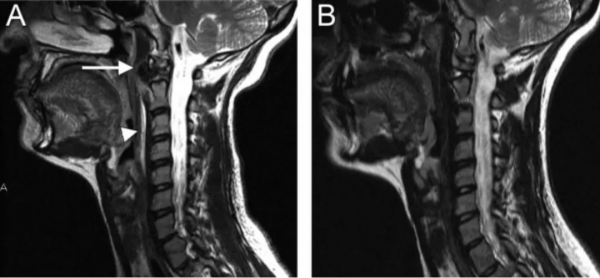

圖:患者8歲,女孩,因嚴重頸部疼痛、活動受限伴左上肢無力、麻木不適2天就診。既往有鎖骨骨折、額部軟組織挫傷病史。查體:頸椎活動受限,左上肢肌力正常,但感覺減退。白細胞、血沉、CRP升高。頸椎側位片和CT平掃提示C6-7椎間盤鈣化(粗箭頭)和後縱韌帶骨化(細箭頭),頸椎MRI提示C6-7水平脊髓明顯受壓。給予頸椎制動、枕頜帶2.5kg頸椎牽引2周。隨後,頸託固定1個月。2年後隨訪複查頸椎CT如下圖,同時上述症狀完全緩解。

圖:2年後複查CT示C6-7鈣化的椎間盤和後縱韌帶骨化都消失了

圖:8歲女孩,因頸腰痛伴左上肢放射痛2月餘就診,頸椎側位片、CT和MRI表現與上述病例類似。

圖:給予保守對症治療(具體不詳)1月後症狀消失。6個月時隨訪可見鈣化的椎間盤和後縱韌帶都消失了。